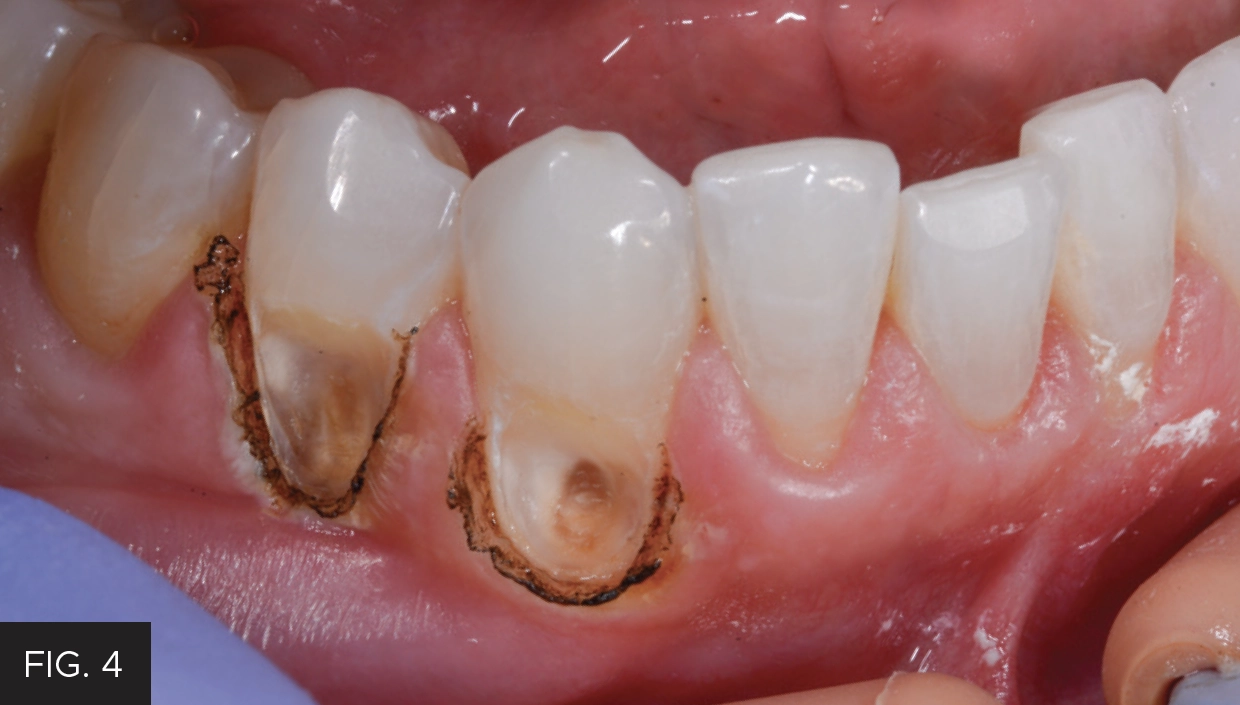

Clinically, the tissue was slightly inflamed due to the presence of decay and bacterial infiltration. This tissue was removed with the Bluewave laser to the level where the decay could be removed, and healthy tooth structure could be adequately isolated and restored. (FIG. 4)